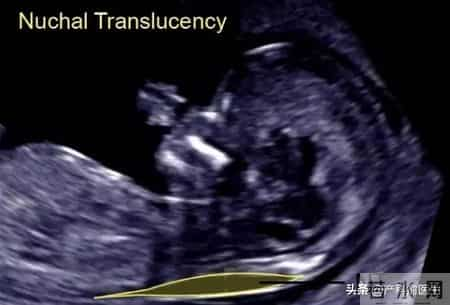

NT 的全称是:颈项透明层厚度(Nuchal Translucency)指的是:胎儿颈后皮下的液体厚度,通过B超测量获得。NT不是诊断,而是筛查。它的意义在于:早期发现胎儿发生染色体异常或结构异常的风险信号。

很多人以为NT只看“厚不厚”,实际上,合格的NT检查至少包括以下内容:NT厚度≤2.5 mm 为正常范围,越厚,异常风险越高(但不是确诊)。 胎儿鼻骨是否显示(非常关键)鼻骨是否存在 / 是否清晰显示,是NT筛查中一个重要的软指标。